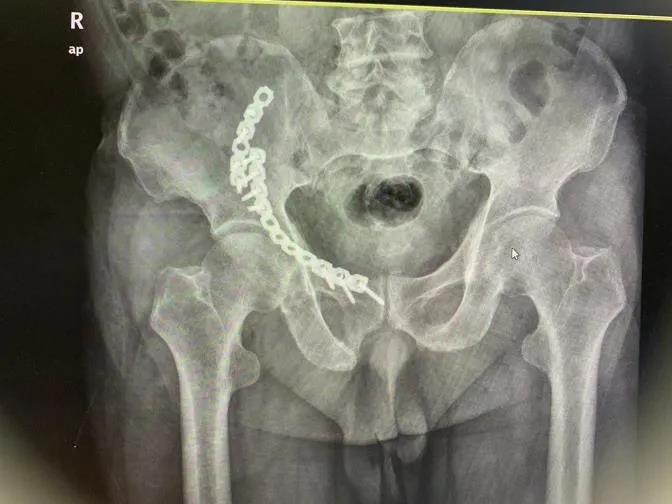

术前影像资料

术后影像资料

拆除内固定后影像资料